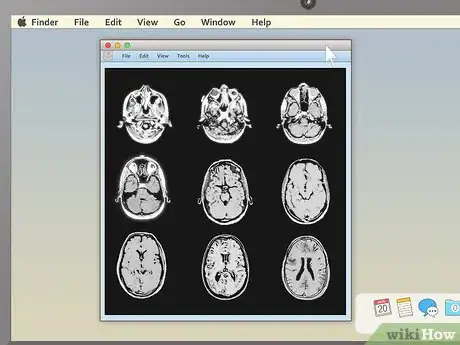

5View the images. Most MRI programs start with a large black space on one side of the screen and a smaller toolbar on the other side. If you see small preview pictures of your MRI images in the toolbar, double click on the image you want to view. It should load a large version of the image into the black area.

- Be patient while you wait for your images to load. Though the viewing programs don't usually look like much, a single MRI image contains a large amount of information, so it may take your computer a moment or two to finish the job of loading it up.

3Pick an appealing series layout. MRI programs almost always have the ability to display more than one image at once. This makes it convenient for doctors to compare different views of the same area or even MRIs taken at different times. For most non-doctors, it's easiest to simply choose a one-image-at-a-time layout and cycle through the images individually. However, there should be onscreen instructions to show two, four, or many more images at once, so feel free to play around with this feature.